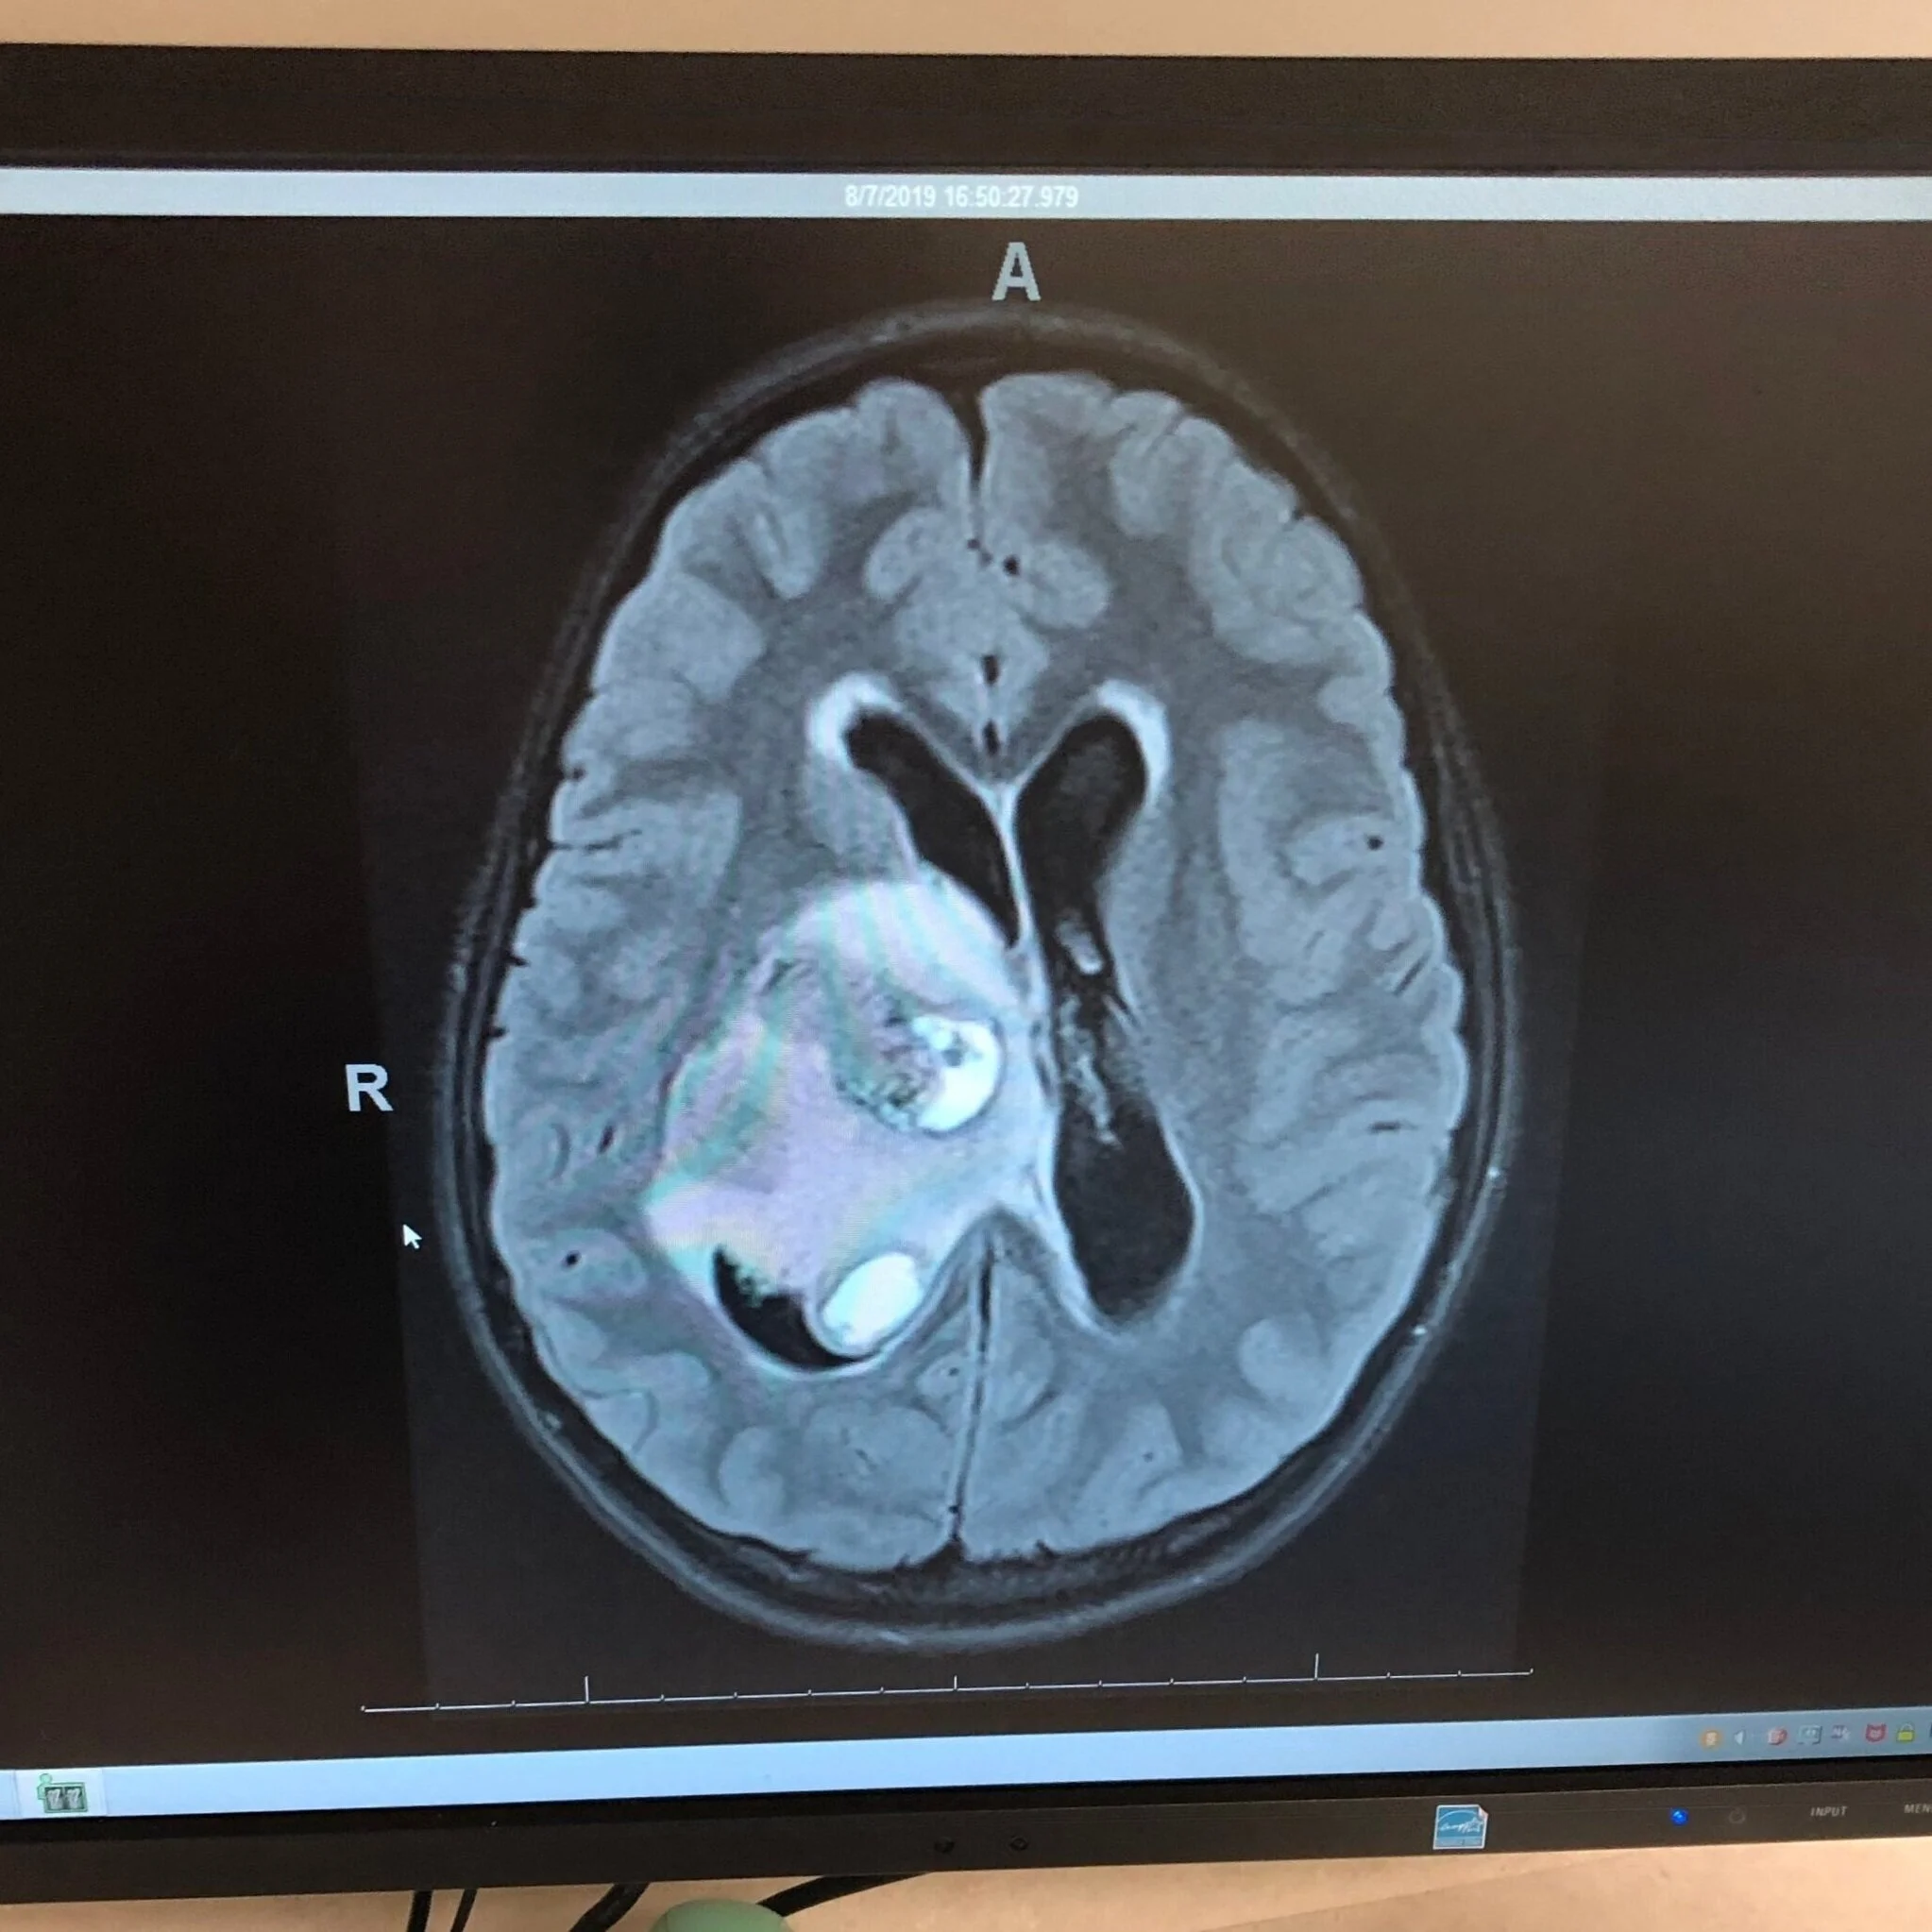

This is what the doctors showed us on the monitor 3 days later. In disbelief and utter horror, I took this picture.

Today, somewhere in the world, a family is looking at a similar image on a computer screen of the DMG that’s growing in their child’s brain. Today, their battle with this monster will begin. For that family, I hope you’ll consider giving to any one of the many organizations and foundations that help fund research for pediatric brain cancer.